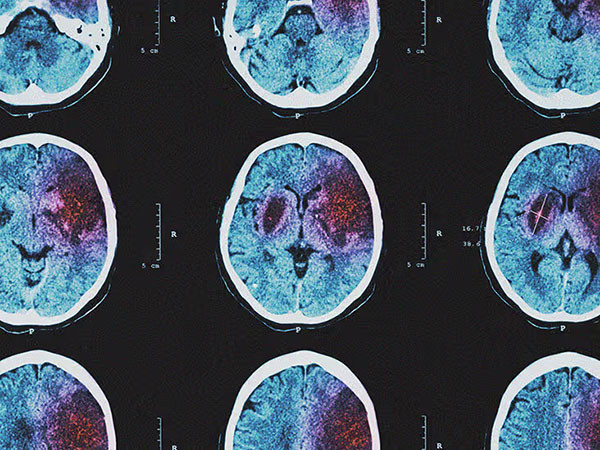

Xuất huyết não là một dạng tai biến mạch máu não xảy ra khi một mạch máu trong não bị vỡ, gây chảy máu vào mô não. Tăng huyết áp là nguyên nhân chính gây xuất huyết não. Máu chảy ra sẽ gây áp lực lên các tế bào não, dẫn đến tổn thương mô não và các triệu chứng tương tự như thiếu máu não: yếu liệt, méo miệng, nói khó, đau đầu dữ dội, chóng mặt, ảnh hưởng đến thị lực, rối loạn cảm giác, khó nuốt, thay đổi tính cách. Tuy nhiên, trong xuất huyết não, đau đầu dữ dội thường xuất hiện đột ngột và rất nghiêm trọng. Cấp cứu và điều trị xuất huyết não đòi hỏi sự can thiệp y tế khẩn cấp tại bệnh viện. Phương pháp điều trị có thể bao gồm phẫu thuật để loại bỏ máu tụ hoặc dùng thuốc để kiểm soát huyết áp. Chụp CT/MRI não bộ là phương pháp chẩn đoán hình ảnh quan trọng để xác định vị trí và mức độ chảy máu. Giống như thiếu máu não, phục hồi chức năng là một phần quan trọng trong quá trình điều trị và phục hồi sức khỏe cho người bệnh.

Giai đoạn quyết định

Giai đoạn quyết định là thời điểm người bệnh được đưa đến bệnh viện và tiến hành cấp cứu. Các bác sĩ sẽ tiến hành các xét nghiệm cần thiết như chụp CT/MRI để xác định loại TMV (nhồi máu não hay xuất huyết não) và mức độ tổn thương não. Điều trị kịp thời, chính xác là chìa khóa để giảm thiểu tổn thương não và cải thiện khả năng phục hồi. Các phương pháp điều trị có thể bao gồm: